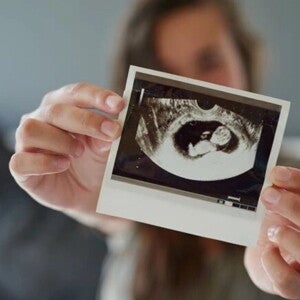

Descubre el Desarrollo del Feto Mes a Mes: Hitos Increíbles

Explora el fascinante desarrollo del feto mes a mes y descubre los increíbles hitos de crecimiento en este emocionante viaje prenatal.

30 semanas de embarazo

Descubre el desarrollo de tu bebé y los cambios que tendrá tu cuerpo.